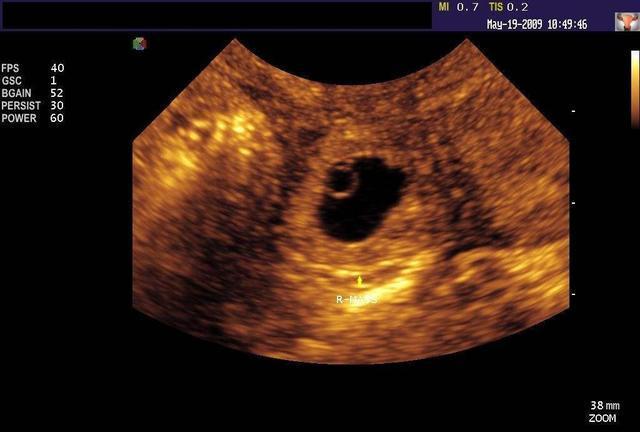

这一检查,出了大问题!在医院的小陈腹部越发的痛,医生给出的检查结果是宫外孕!医生更是感叹道,还好来得及时,一般人的正常血量在4400ml左右,可你的腹部血量已经占了一半左右,这要是发现得晚,后果可不是开玩笑的! 等到林先生赶到医院时,医生问了两口子平时的生活习惯以及性习惯,这下才知道,两人平时采取的避孕措施竟然是通过药物! 原来,林先生不喜欢使用避孕套,认为避孕套影响感觉,于是便让妻子长期吃避孕药来避孕。但避孕药也有失败率,这不,就体现在妻子身上了。

实际上,在当今,宫外孕还算是较为常见的疾病,但发病率最高的年龄段在30岁以后,20~30岁的女子发病较少。小陈之所以会发生宫外孕,医生在一系列的检查之外,综合判断就是长期服用避孕药所致! 下面的几个坏习惯,还希望大家一定要避免,尤其是男性! 1、 不重视卫生 我们都知道,女性比男生更易被感染,就像10个已婚女人中可能有9个患有妇科病,而追其根源,排除其他原因,大多都与夫妻生活时的一些坏习惯有关,尤其是卫生问题! 如同房之前没有先清洁的习惯,这是极为不可取的,人体性部位比其他部位更容易滋生细菌,而且潮湿的温度更是培养菌种的绝好环境,不注重卫生就同房,菌种找上门也是意料之内的事情!